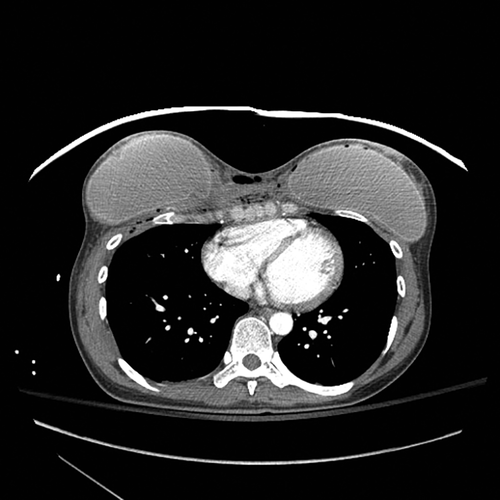

Figure 8. Аксиальная компьютерная томография (КТ) показывает, что пуля проходит по средней линии, спереди от грудины и входит в правую капсулу молочной железы.